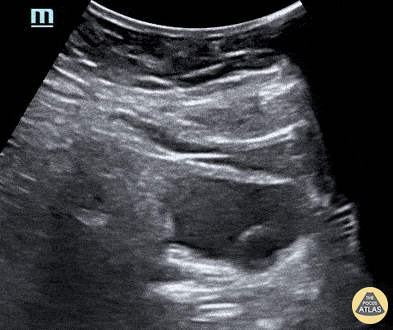

34-year-old female with a history of type 1 diabetes and recurrent urinary tract infections presenting to the emergency department with complaints of left flank pain and dysuria for two days. CT scan showed a 5.4 x 5.8mm obstructive calculus in the left lower ureter and moderate left hydronephrosis. POCUS additionally noted an anechoic, cystic structure projecting into the bladder, consistent with a ureterocele. Shown here is the transverse bladder scan image. Ibrahim Baida, MS4, @ibbaida Ian Keck, PGY-3 Dax Spencer, PGY-1 Central Michigan University College of Medicine